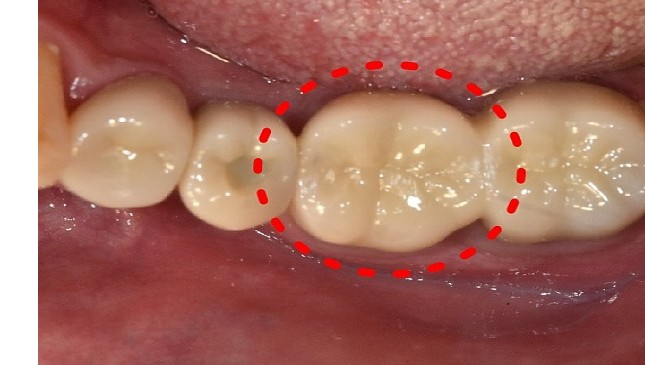

치아살리기 치료 전후 사진

잇몸 전체가 무너져 동시다발적으로 죽어가던 치아들을 한꺼번에 살려 냅니다.